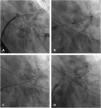

We present the case of an 85-year-old male patient with a history of digestive hemorrhage with hypovolemic shock and hemorrhagic stroke with ad integrum restitution. He had permanent atrial fibrillation (CHA2DS1-VASc: 6 and HAS-BLED: 5) and was receiving indefinite oral anticoagulation with Apixaban®. After the last episode of bleeding, the patient was referred for left atrial appendage closure and underwent a successful 24 mm Watchman device implantation (Boston Scientific, MN, USA), with the presence of a small leak <3 mm that was managed conservatively. Two years after the implant, he suffered a new episode of ischemic stroke in the frontal lobe. Transesophageal echocardiography (TEE) revealed the presence of two significant leaks >5 mm, one on the posterosuperior side and the other on the anteroinferior side (Figure 1, Video 1-2). Due to high hemorrhagic risk, the patient underwent percutaneous closure of the leaks.

A: Transesophageal echocardiography (TEE) image showing anteroinferior leak (yellow arrow) and posterosuperior leak (white arrow). B: Transesophageal echocardiography with TEE image showing color flow Doppler through the posterosuperior leak. C: Computed tomography image showing leaks on both sides of the device.